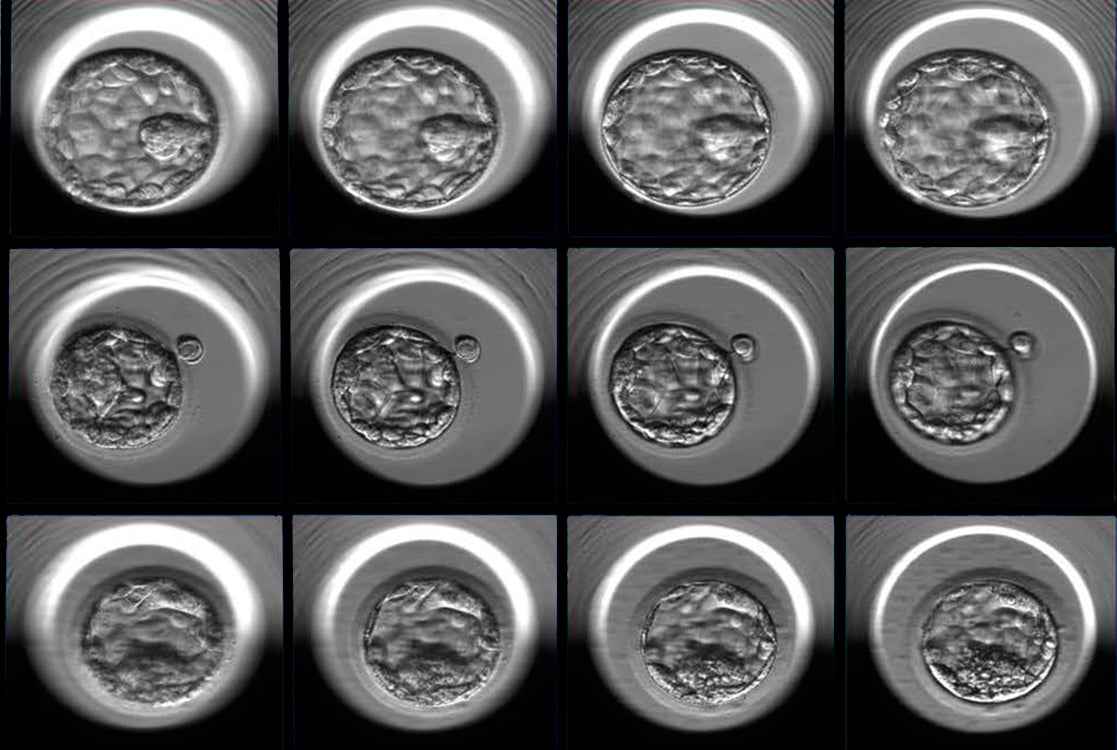

“This is where the miracle happens. The egg is stabilised under the microscope by means of the holding pipette, and a single sperm is injected into the centre of the egg. Now the sperm will not have to work so hard to get inside the egg, but still needs to deposit its DNA into the egg for fertilisation to take place. I will repeat this process with as many eggs as possible. The fertilised eggs are then placed into an incubator that keeps the temperature and pH steady, at the same level it would be in a mother’s womb. After three days, we will be able to see how many embryos have developed, and are healthy enough to be either transferred to Mommy and/or be frozen stored for later transfer. I enjoy sending the parents updates, photos of each step, so they can experience the ‘conception’ and daily development of their baby as well.”